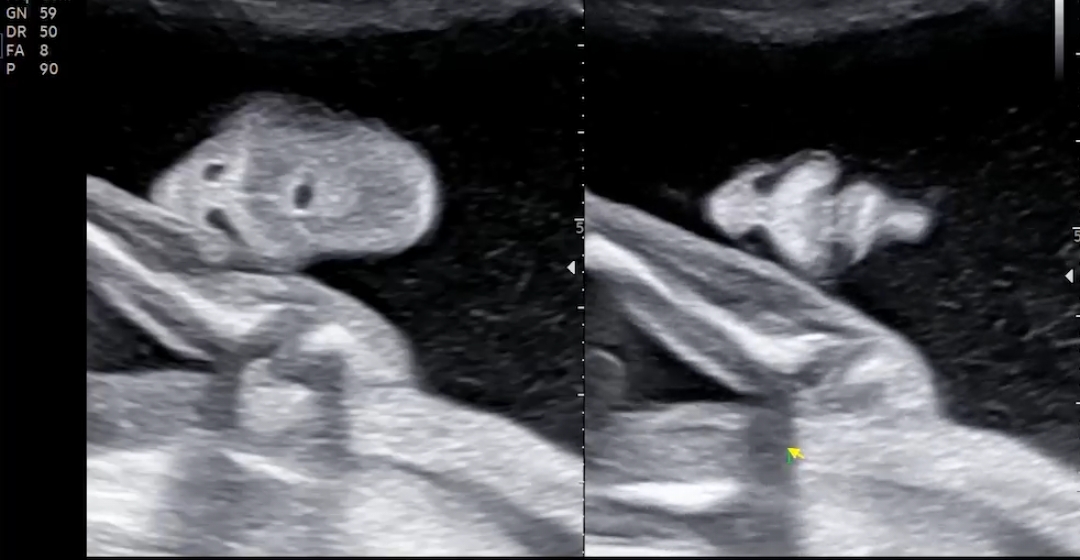

다음은 아기 옆모습!! 너무 귀엽고 기특하고 신비롭고 오만감정이 들었어요. 신기함이 제일 큰 거 같아요.

콧대가 높아보여서 기분이 좋았어요ㅋㅋ도치맘.. 그 와중에 손 옆에 주먹 쥐고 있는거 귀엽고욘

마지막으로 예쁜 옆모습 한 번 더 보고 정밀초음파 마무리~